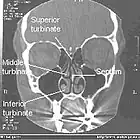

Frontalschnitt einer Computertomographie der Nasenhöhle und Nasennebenhöhle -

Das von einer Schleimhaut mit Flimmerepithel ausgekleidete Cavum nasi wird jeweils zwischen Boden und Dach der Nasenhöhle durch knöchern gestützte Nasenmuscheln (Conchae nasales) etagenartig in die Nasengänge (Meatus nasi) untergliedert. Die mediane Wand bildet das Septum; in der seitlichen Wand liegen Eingänge zu den Nasennebenhöhlen. Nach hinten öffnen sich die Nasenhöhlen über die Choanen zum nasalen Teil des Rachenraums.

Beim Menschen sind meist drei Nasenmuscheln (lat. conchae nasales) zu unterscheiden:

- obere Nasenmuschel (Concha nasalis superior, bei Tieren Concha nasalis dorsalis)

- mittlere Nasenmuschel (Concha nasalis media)

- untere Nasenmuschel (Concha nasalis inferior, bei Tieren Concha nasalis ventralis)